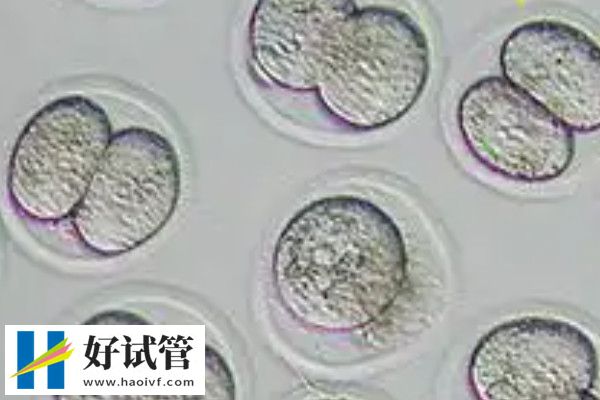

根据相关了解,就成功率而言,养囊后移植的妊娠率要比攒胚胎后的种植数据更高一些,但要注意的是,养囊风险是很高的,很有可能会出现一半以上胚胎停止发育的情况,情况严重的话,甚至还可能会出现全军覆没的情况。另外,攒胚胎和养囊的区别还是很大的,其中攒胚胎是将已经培育好的胚胎进行冷冻保存,而养囊则是继续在培养皿中进行培育。

而目前该项目中有多余胚胎的情况下有两种选择,分别是攒胚胎和养囊,其中养囊的成功率会更高一些,因为囊胚的潜力更大,同时也更适合人体生理需求。

虽然每个胚胎都有成功的可能,但从大数据来说,囊胚的成功率会更高。这也是为什么要养囊的原因。就如一场马拉松比赛,有些“胚胎选手”能跑500米,有些能跑1000米。在所有胚胎都跑到500米时,看起来都是一样优秀,但如果让“胚胎选手”们继续跑,这时候没有能力跑到1000米的就会逐渐被淘汰掉,剩下有能力跑到终点的,就是养出来的“囊胚”。

攒胚胎指将取卵后获得的胚胎通过冷冻技术保存起来,在适当的时候再进行移植。这包括玻璃化冷冻法和程序冷冻法,旨在保护胚胎的生命力,使其处于休眠状态。而养囊指将取卵后获得的胚胎继续培养至囊胚阶段,再进行移植。囊胚是胚胎进一步发育的产物,通常在卵子受精后的第五到七天形成。

攒胚胎优点体现在灵活性和提高成功率,其中灵活性方面可以根据患者的身体状况和子宫环境选择合适的移植时间。而提高成功率则是因为通过冷冻保存,可以给予患者第二次移植的机会。而养囊囊胚发育阶段更为成熟,具有更高的着床能力。不仅如此,通过养囊过程,可以淘汰发育不良的胚胎,选择质量更好的胚胎进行移植。

攒胚胎的复苏率低,因为冷冻过程中可能会损伤胚胎,而且冷冻技术的不同可能影响胚胎的保存质量和复苏率。而养囊可能会导致部分胚胎无法发育至囊胚阶段,从而引起可利用的胚胎数量减少。